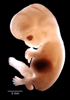

Carnegie Stage 22 (54 post-ovulatory days)

Most embryos at stage 22 are approximately 54 postovulatory days old and measure 25-27 mm in length. Distinguishing criteria for this stage include clear formation of the external ear, the hands begin to extend ventrally beyond the body wall, the fingers of one hand may overlap the fingers of the opposite hand, thickened eyelids just begin to cover the outer margins of the eye, and the superficial vascular plexus of the head now extends about three-quarters of the way above the eye-ear level.

Photographs